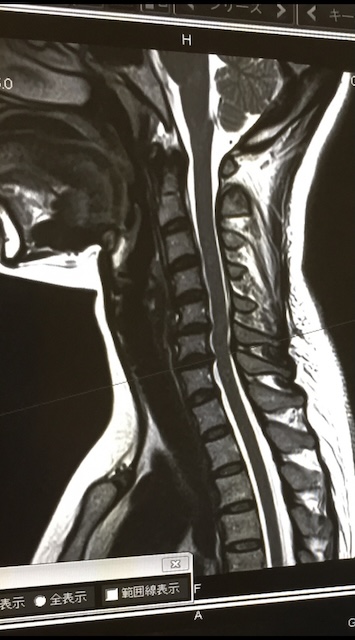

(注:画像はフリー素材です)

しかし痛みが引かなかったため総合病院を受診し、MRI撮影を行ったところ椎間板ヘルニアの診断を受けた。作用が強いボルタレンを処方されて、当院来院時にも服用しているとのことであった。病院では神経根ブロック注射を勧められたが、首に注射を打つことに抵抗があったためその前に症状が改善できる手段がないか?と検索したところ当院のカイロプラクティックが表示され、試してみようと思い来院した。

この方の場合首の位置が前方にスライドしており、頚椎のストレートネック=湾曲減少によって頭部の重さが垂直な圧で椎間板に負担をかけた影響であると考えました。

上記に加え、第5頚椎の左回旋(5番目の頚椎が捩れている)状態があったため第5頚椎にヘルニアを起こしたと考えられる。